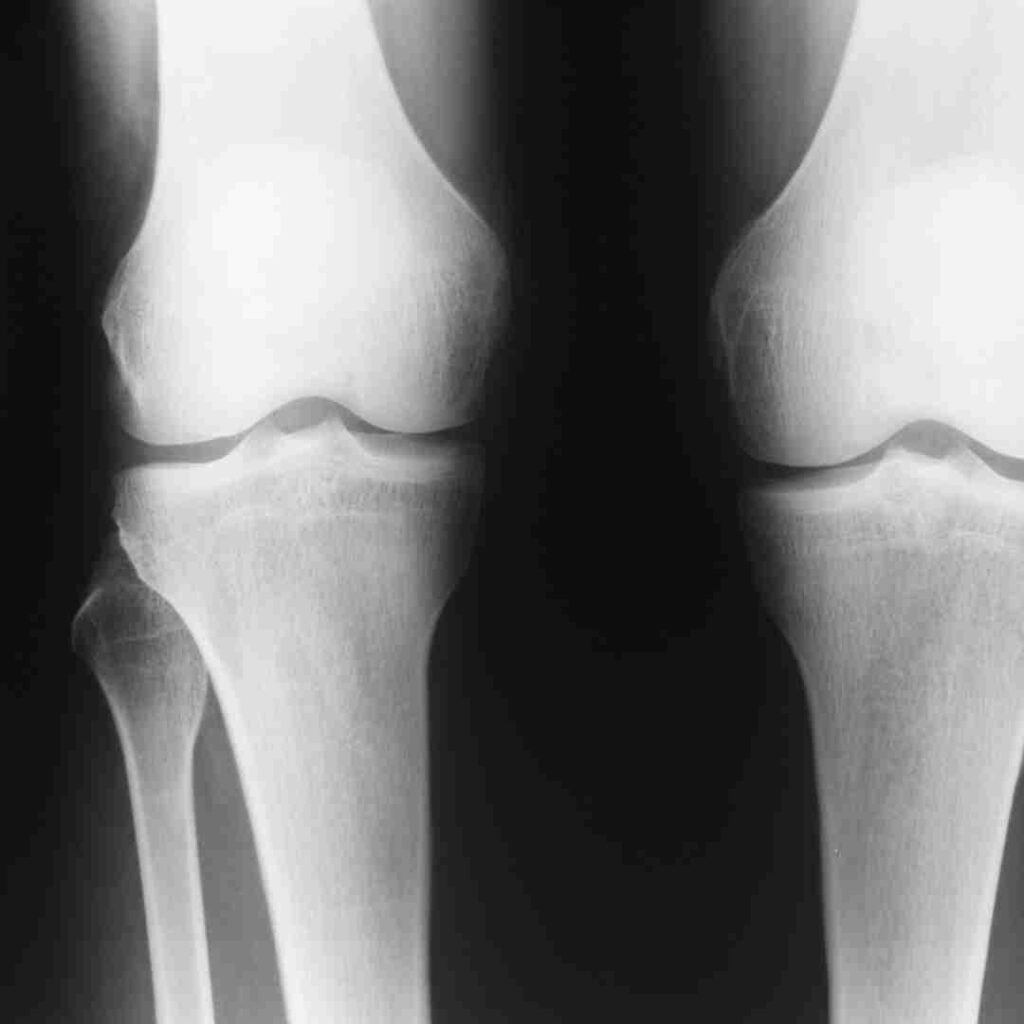

Diagnosis of Complex Fractures

X-ray for implant position

CT or MRI if needed

Doctors use X-rays, CT scans, MRI, and physical examination to assess implant position, bone health, and joint stability.